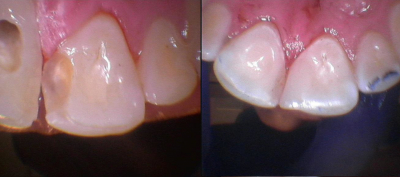

Gallery

Galeria